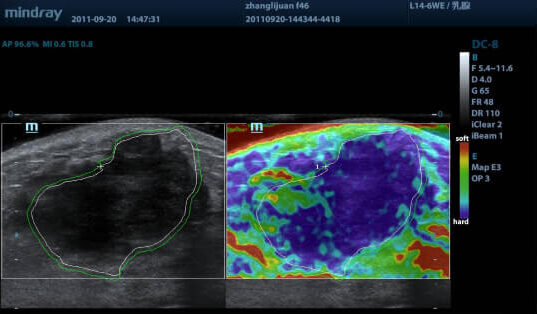

Эластография — технология УЗИ, которая позволяет проанализировать эластичность и плотность тканей. Здоровые ткани обычно упругие и мягкие, а патологические — жесткие.

Эта опция позволяет выявлять онкологию на ранних стадиях, узловые образования и другие патологии. Благодаря этому нет необходимости прибегать к биопсии.

Компрессионная эластография (NTE) позволяет оценить эластичность поверхностно расположенных тканей (например, молочных и щитовидной желез) за счет дополнительного давления датчиком.

- наличие наглядной цветной карты плотностей тканей;